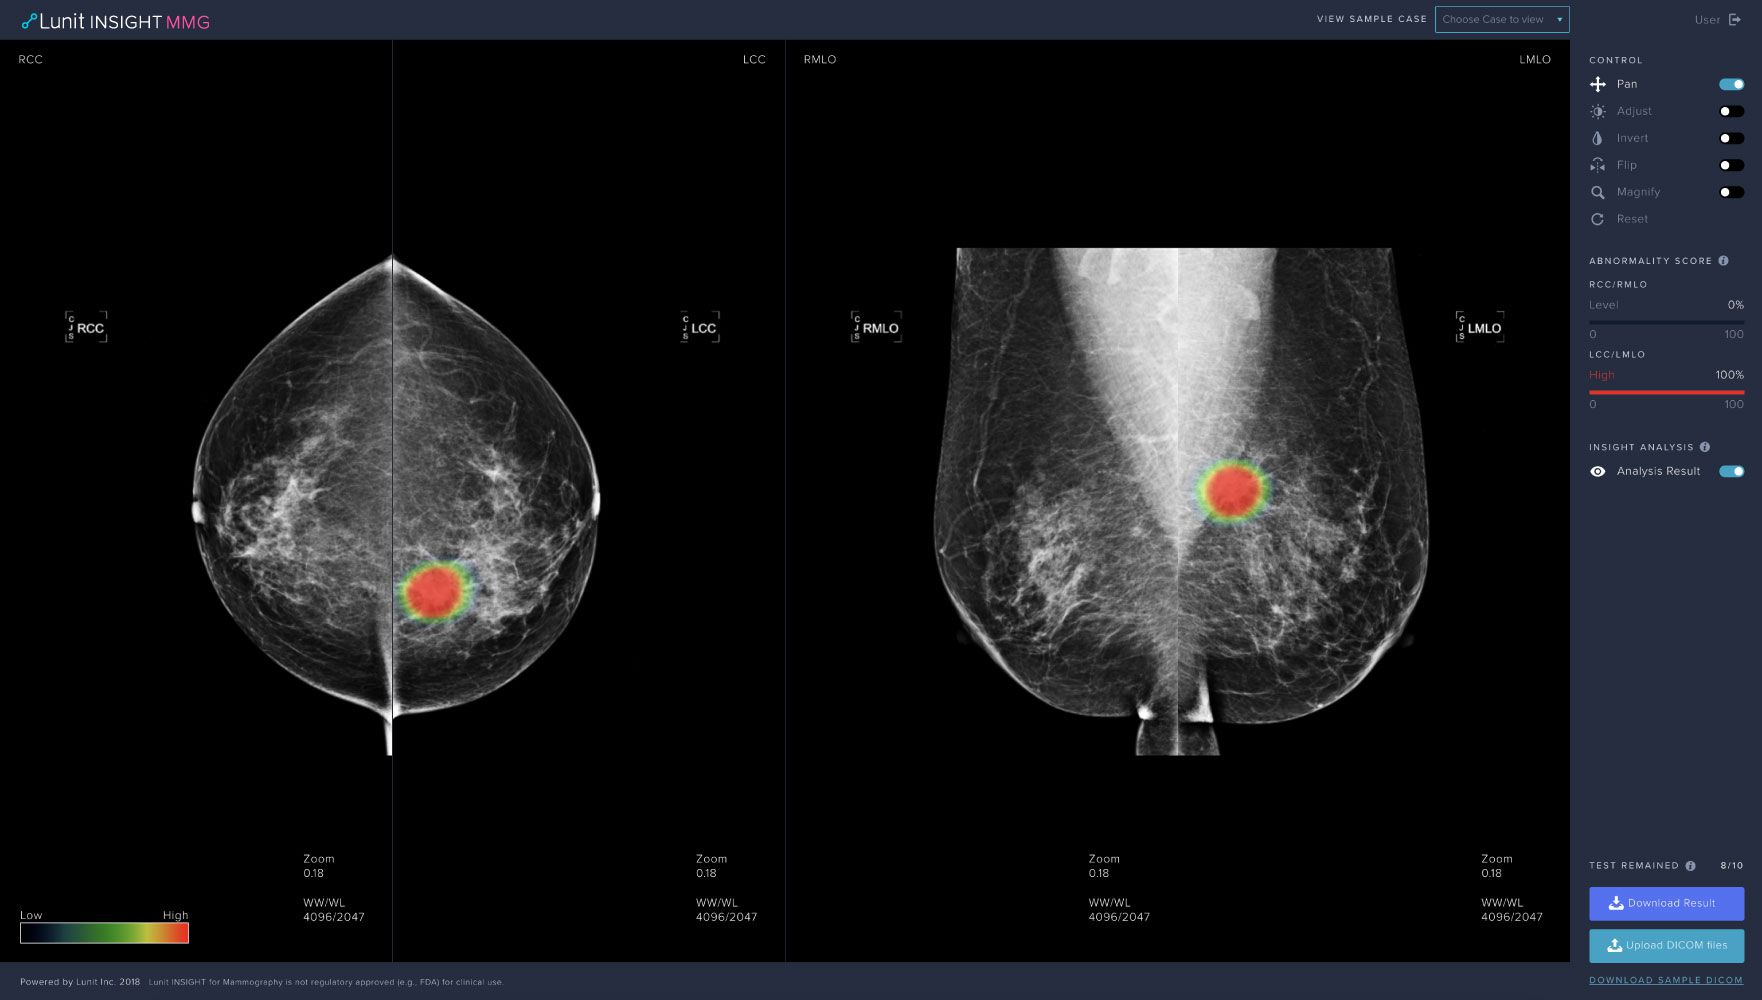

Product image of Lunit INSIGHT MMG

Lunit INSIGHT MMG is one of the company’s most mature radiology products which analyzes mammography images with high accuracy. It provides the location of lesions suspicious of breast cancer and an abnormality score that reflects the AI’s confidence of the existence of detected lesions.

The product is trained with a large-scale data of more than 240,000 mammography cases that include up to 50,000 breast cancer cases, and is known to show excellent performance in finding breast cancer at an earlier stage.